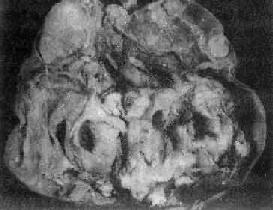

三、卵巢生殖细胞肿瘤卵巢生殖细胞瘤占卵巢肿瘤的15%~20%,20岁以下的卵巢瘤患者约60%属此类,所幸的是95%的生殖细胞瘤为良性囊性畸胎瘤。患者越年轻,所发生肿瘤的恶性程度可能越高。 (一)卵巢畸胎瘤 来源于卵巢多能的生殖细胞,其良恶性程度主要取决于瘤组织的成熟度,因此将畸胎瘤分为成熟型和未成熟型两大类。 1.成熟型畸胎瘤(teratoma,mature type) 多数为囊性,称囊性畸胎瘤,属良性,大多为单侧性。在卵巢生殖细胞瘤中最多见,占卵巢畸胎瘤的97%~99%,占所有卵巢肿瘤的20%。多发生于生育期妇女。 【病变】 肉眼观,肿瘤多为囊性、中等大小,表面光滑,囊内含毛发团及皮脂样物(图13-22)。囊壁较厚,内侧常有一处突起的结节或我称头节,表面被覆鳞状上皮,结节内常有毛发、牙或骨质等。肿瘤多数为单房。镜下,可见到三胚层各种类型的成熟组织,其中以皮肤、皮脂腺、汗腺、毛囊及脂肪最多见;其次为软骨、神经胶质、神经细胞、骨及呼吸上皮;其他如甲状腺、胃肠上皮及牙等较少见。

图13-22 卵巢囊性畸胎瘤 囊内充满含有毛发的黄色油脂样物 囊性畸胎瘤预后好,少数可发生恶性变,最常见者恶变为鳞癌。恶性变常发生在囊壁内头节附近,故检查时应注意取材部位。 2.未成熟型畸胎瘤(teratoma,immature type)此型较少见,仅占卵巢畸胎瘤的1%~3%。多见于25岁以下的年轻患者。 【病变】 肉眼观,肿瘤多为单侧性,体积一般较大,结节状,切面多为实性,夹杂有单个或多个大小不等的囊性部分。实性部分常为杂色,灰白、棕色或黄色,质软而脆,常有出血坏死。镜检可见由三胚层分化而来的未成熟和成熟组织混合组成。常见的未成熟组织为神经组织,如原始神经上皮和室管膜等结构及各种胚胎性组织,如胚胎性骨、软骨及肌肉等。皮肤组织较成熟型少见。其中可混杂一些各胚层的成熟组织。 未成熟型畸胎瘤常合并其他生殖细胞肿瘤,如内胚窦瘤、无性细胞瘤及绒癌等。一般说,肿瘤组织中未成熟组织及胚胎性组织的含量与临床恶性程度有关。病理上根据未成熟组织的含量,可分3级:①1级,主要为成熟组织,有少量未成熟组织,没有神经上皮或每一切片中神经上皮不超过一个高倍视野;②2级,有较多未成熟组织,每一切片中所含神经上皮不超过1~3个高倍视野;③3级,未成熟组织量多,每一切片中神经上皮超过4个高倍视野。 预后 未成熟畸胎瘤的预后与病理分级、临床分期密切相关。复发及转移者多为2、3级。转移的部位多在盆腔及腹腔内,远处转移极少。 (二)无性细胞瘤 无性细胞瘤(dysgerminoma),较少见,约占卵巢恶性肿瘤的1%~2%,多见于10~25岁年轻妇女。 【病变】 肉眼观,常为单侧性,约10%为双侧性。肿瘤多为圆或卵圆形,表面光滑,质韧。切面多为实性,有不同程度的出血坏死或囊性变,色灰红、暗红及棕黄色。镜下,与典型的睾丸精原细胞瘤非常相似,瘤细胞体积大而圆,比较一致,胞浆因含糖原而透明。核大,圆或卵圆形,大小形态一致,小泡状,核仁明显,核分裂像常见。瘤细胞排列成片块、巢状或条索。瘤细胞间常有不等量的淋巴细胞浸润及多少不等的纤维组织。由于肿瘤细胞形态和组织化学特性与未分性别的原始生殖细胞极相似,故命名为无性细胞瘤。 本瘤预后较好,对放射线敏感,5年生存率90%~95%。约5%病人对侧卵巢在显微镜下才能发现肿瘤,因此手术时必须进行活检,作冷冻切片检查。 肿瘤可直接蔓延扩散至盆腔附近器官及通过淋巴系播散到腹膜后及主动脉旁淋巴结等,晚期也可经血行播散到肺及肝等。 (三)内胚窦瘤 内胚窦瘤(endodermal sinus tumor)又称卵黄囊瘤(yolk sac tumor),来源于多能的生殖细胞,向胚外结构方向分化而形成的一种高度恶性的生殖细胞肿瘤。多见于儿童及年轻妇女,平均年龄18岁。除卵巢外,还可发生于骶尾、腹膜后、纵隔、松果体等处。 【病变】 肉眼观,肿瘤多为单侧性,以右侧为多,一般体积较大,平均直径为15~25cm,圆或卵圆形,表面光滑。切面多为实性,质较脆,灰白或粉白色,常有出血坏死及囊性变。镜检,组织形态较复杂及特殊,主要特征有下列几点:①网状结构,是最常见的形态,由星芒状的瘤细胞形成疏松网状结构(图13-23),其中有微型小囊或间隙,囊腔被覆扁平或立方细胞,这种结构类似胚外中胚层结构;②内胚窦样结构,立方或柱状的瘤细胞成单层排列,包绕毛细血管,形成一血管套样结构,这种结构横切面很像肾小球,称为Schiller-Duval小体,这种小体和大鼠胎盘内的Duval内胚窦结构相似,这种结构可能是由卵黄囊衍生演变而来;③多泡性卵黄囊样结构,特征是由扁平上皮、立方或低柱状的瘤细胞形成大小不等的囊腔,其间隔以致密的结缔组织或疏松的粘液样间质,这种结构与胚胎时期的卵黄囊(胚外内胚层)相似;④在瘤细胞内及瘤细胞间隙可见PAS阳性的大小不等的嗜酸性小滴,免疫组化显示这种小滴含有甲胎蛋白(AFP),正常情况下,卵黄囊可合成AFP;⑤可见腺样、乳头状及实体细胞团结构等。